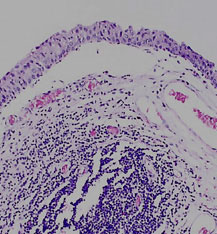

The mucosa is irregularly separating from the underlying submucosa due to post mortem autolysis.